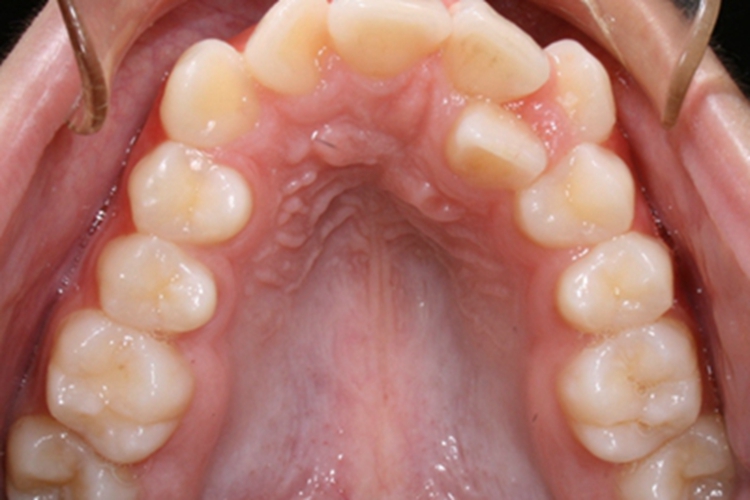

阻生牙可表现为在牙列的两侧有牙齿萌出,与尖牙易位,使牙齿排列不齐,出现前后生长,且生长歪斜的情况。

对于阻生牙牙齿并排生长的情况,首先明确阻生牙齿发育情况是否正常,是否存在牙根歪斜、短根等情况,以此决定牙齿是否保留。

发育正常的阻生牙可不进行治疗,只需要保持良好的口腔清洁习惯,避免龋坏。而对于发育异常的阻生牙或正畸治疗需要矫治的阻生牙,通常可以考虑将阻生牙拔除。